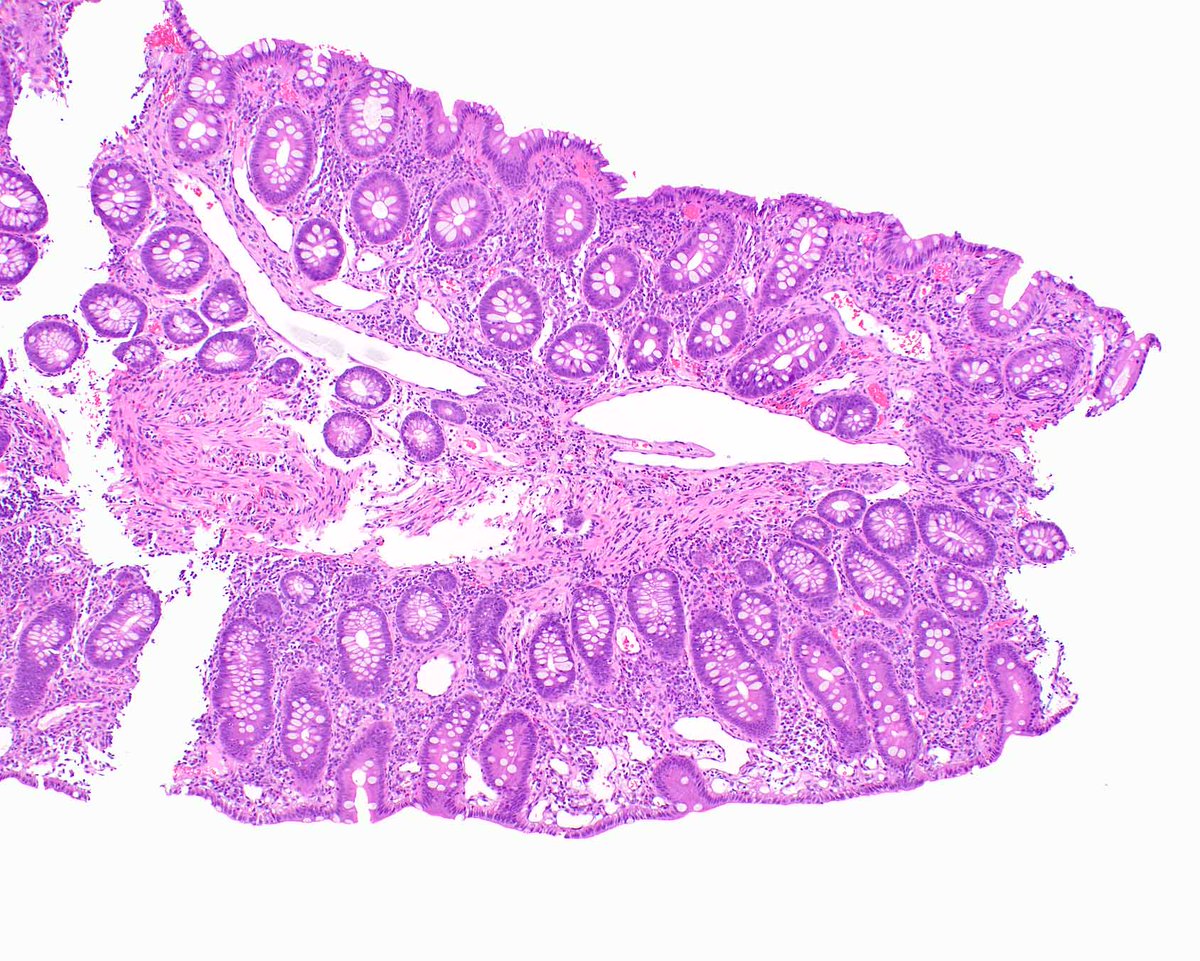

Oxyntic mucosa pseudopolyp. In patients with autoimmune gastritis (pernicious anemia pattern of injury), small foci of undamaged mucosa can appear as polyps because the surrounding mucosa is atrophic and flattened. Krasinskas AM, et al. PMID: 12548171.